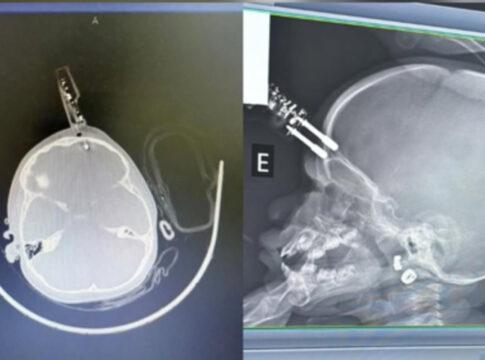

Compartilhar Facebook Twitter Email Copy Link WhatsApp Menina de 1 ano se acidentou após cair da cama enquanto a mãe estava no banheiro Fonte: